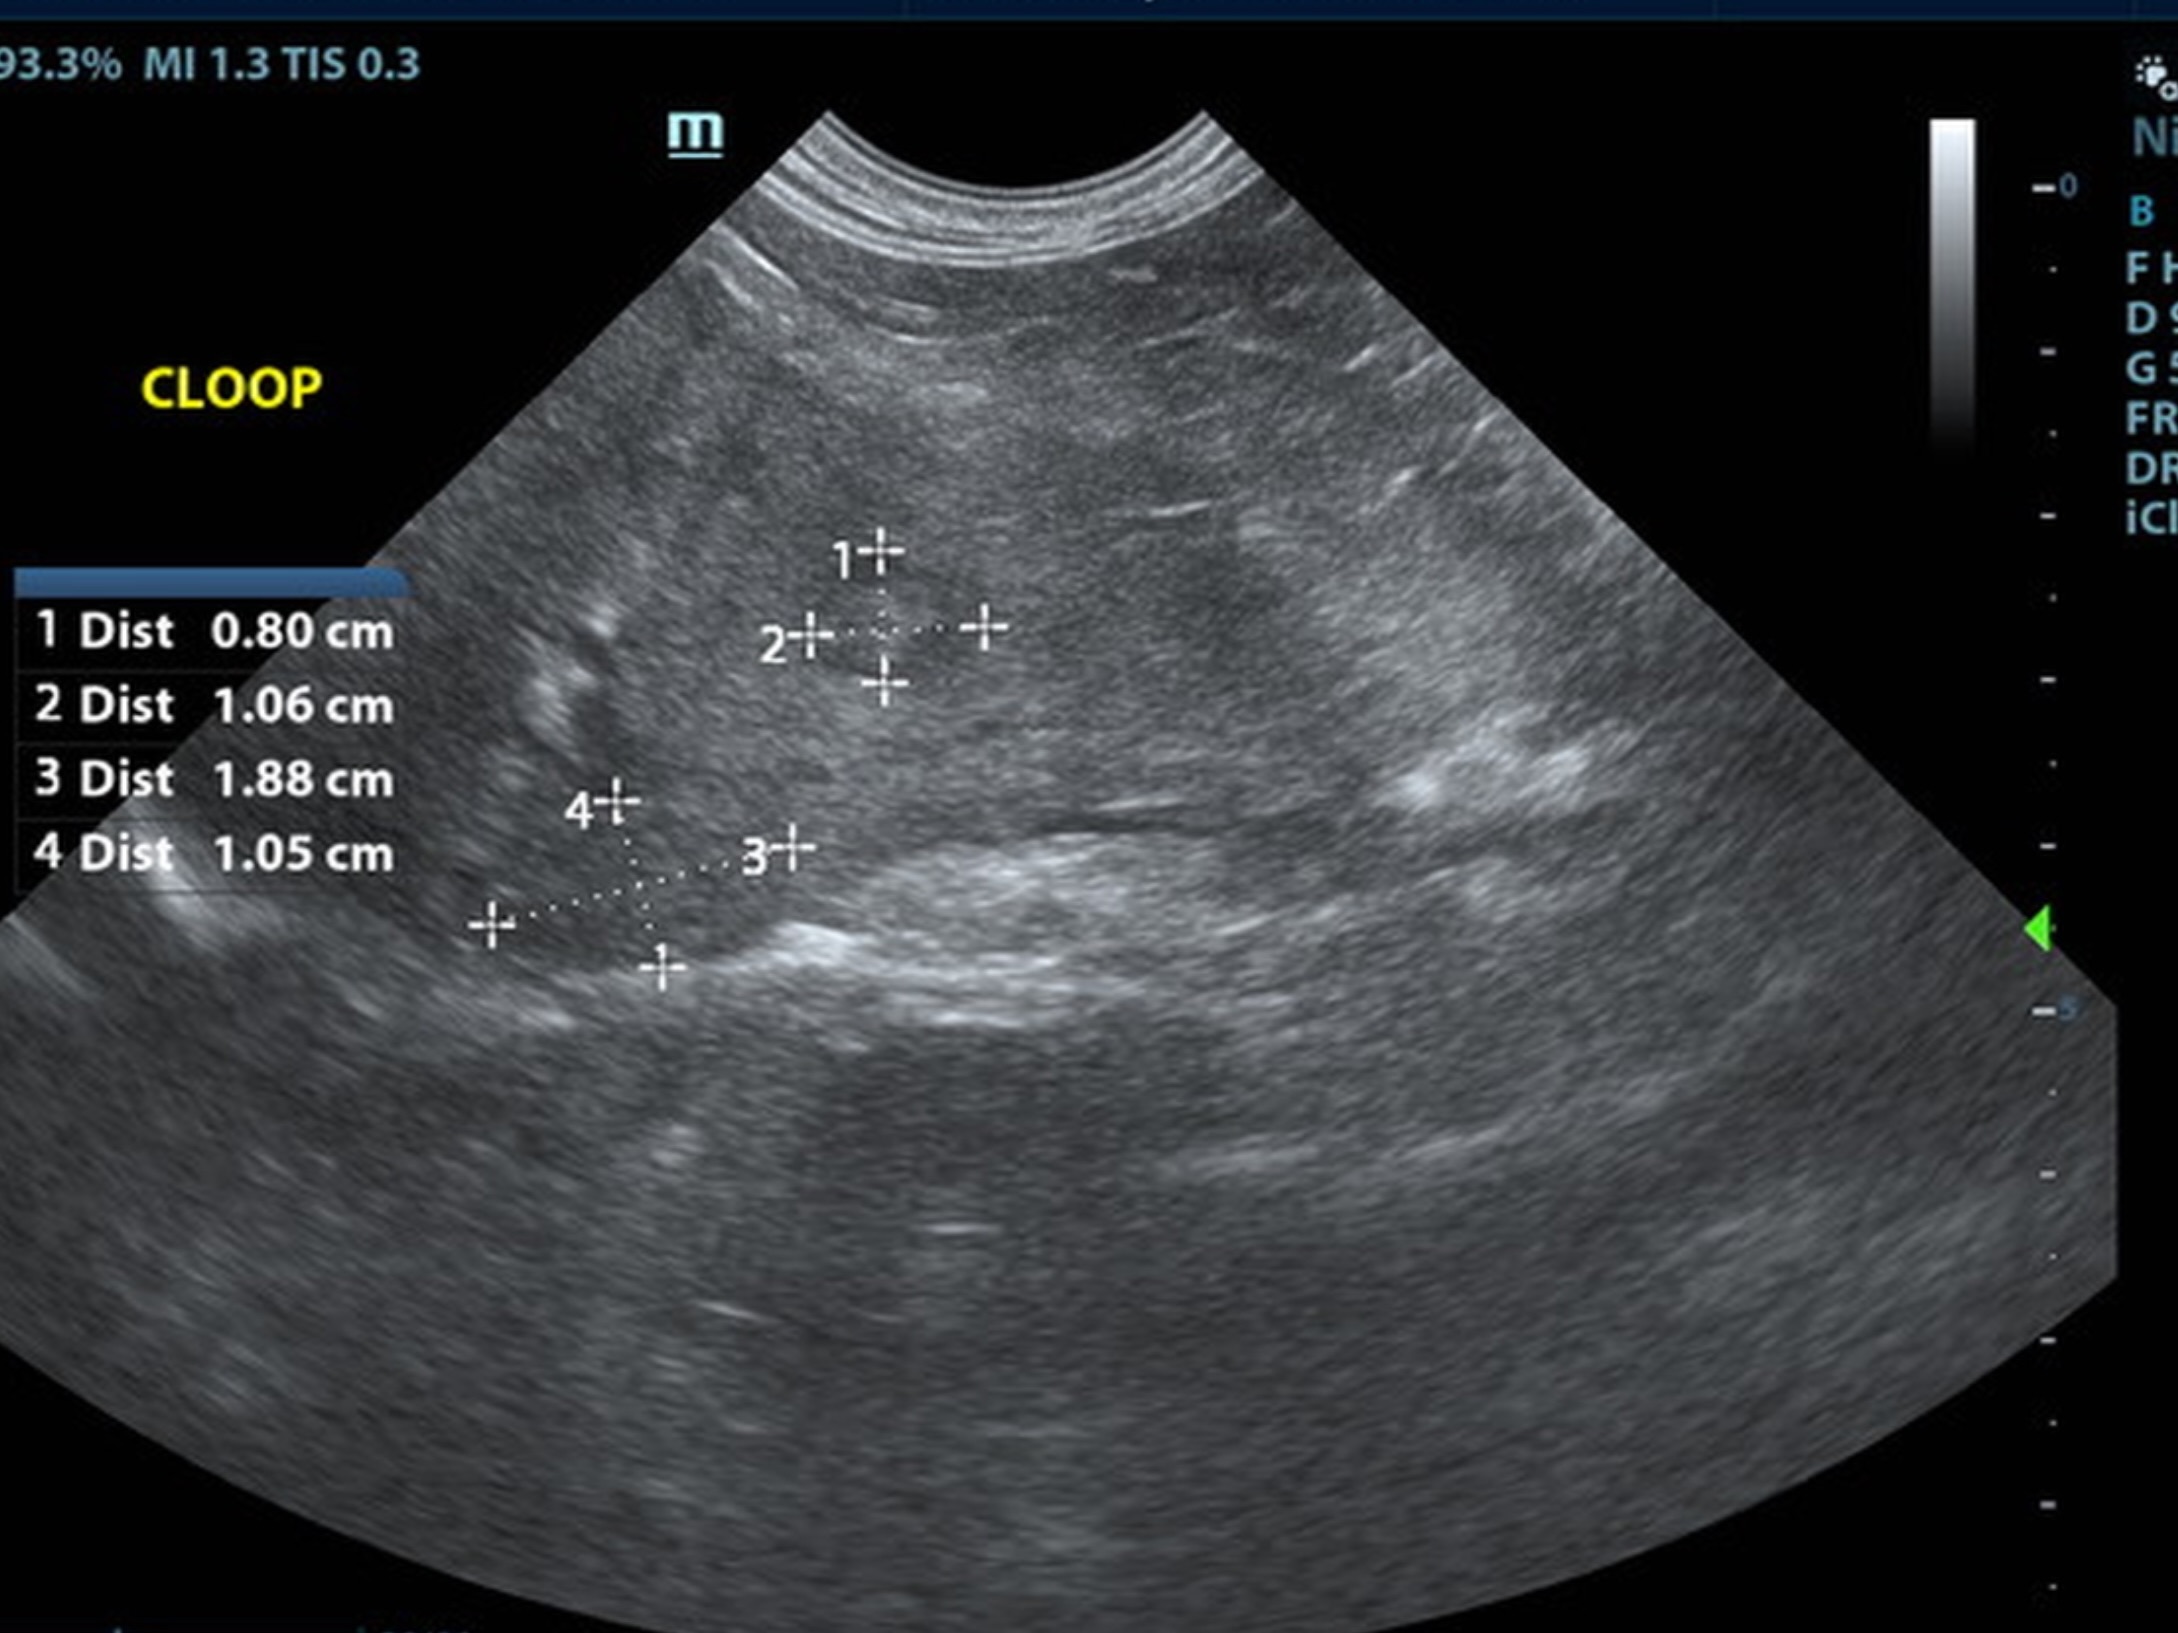

Mild uniform prominence of the gastric mucosa as well as areas of “ropey” small intestinal wall. Hypertrophied mscularis with inverted normal ratio (1:3). Submucosa slightly irregular, thickened and hyperechoic suggestive of low grade chronic inflammation. Probable IBD with low possibility of early neoplastic event such as lymphoma or less likely dry form FIP. Consider full thickness biopsies via open lapartotomy. Reactive mesenteric lymph nodes measured 1.85 x 0.44.